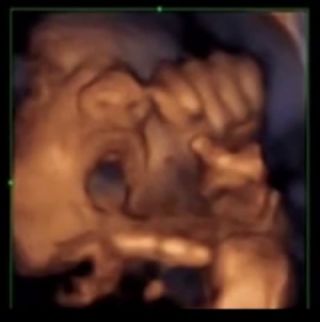

anne karnindaki bebekler muzik sesine tepki verdi